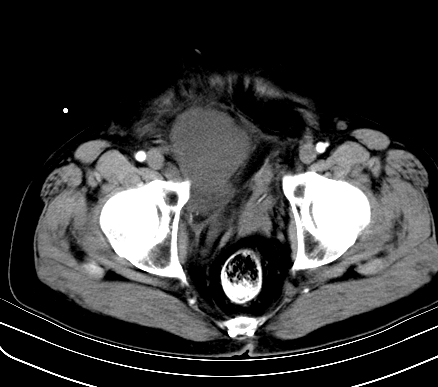

标题: CT19729B:男,74岁,因腿疼就诊,查体触腹部肿物,

增强扫描

延时期

【ct表现】

1、肿块巨大,往往位于腹膜后,长大后才引起症状而就诊;那么位于腹膜后的肿瘤80%为恶性肿瘤。

2、实性肿瘤,增强扫描轻度不均强化,实性肿瘤一般不是好东西。

3、肿瘤边缘似见少许脂肪样密度。

4、腹膜后未见肿大淋巴结,但肿瘤于临近的肠管及组织接触紧密。

【诊断】

腹部占位,考虑位于腹膜后的恶性肿瘤,脂肪肉瘤(实体型)可能性大。

术后病理结果:腹膜后脂肪肉瘤。